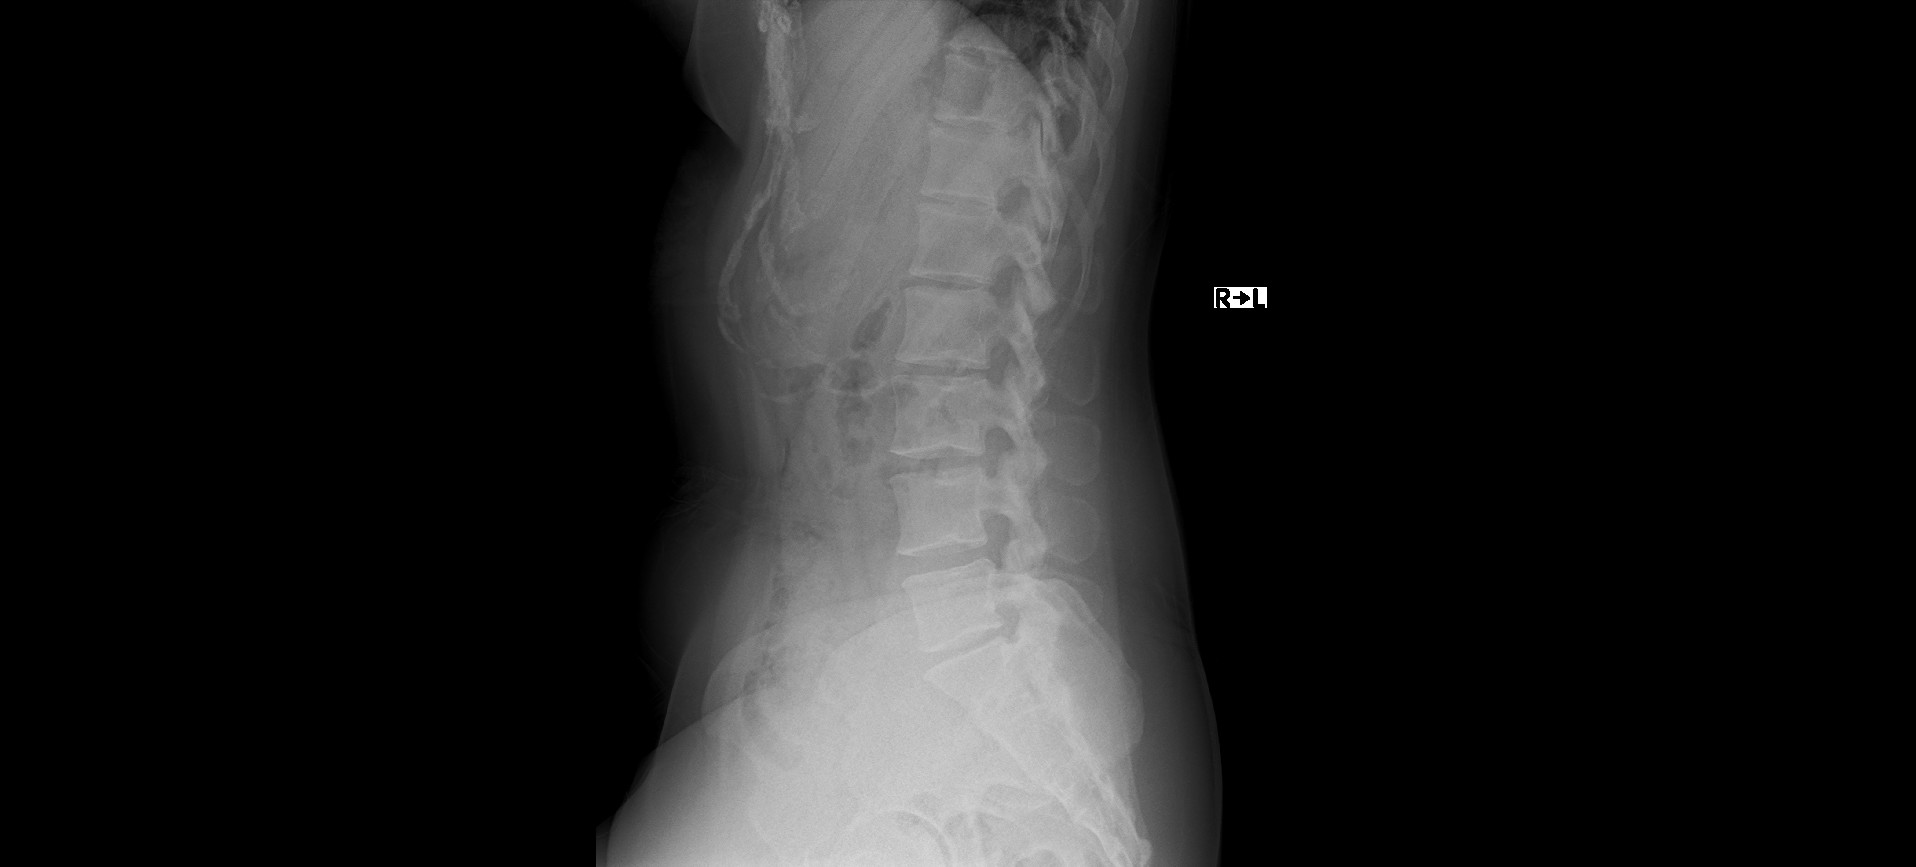

レントゲンでは、ファーガソン角が25度、正常角と比べ減少しており腰椎の前彎が減少している。椎間板はD2~3の変性がみられた。